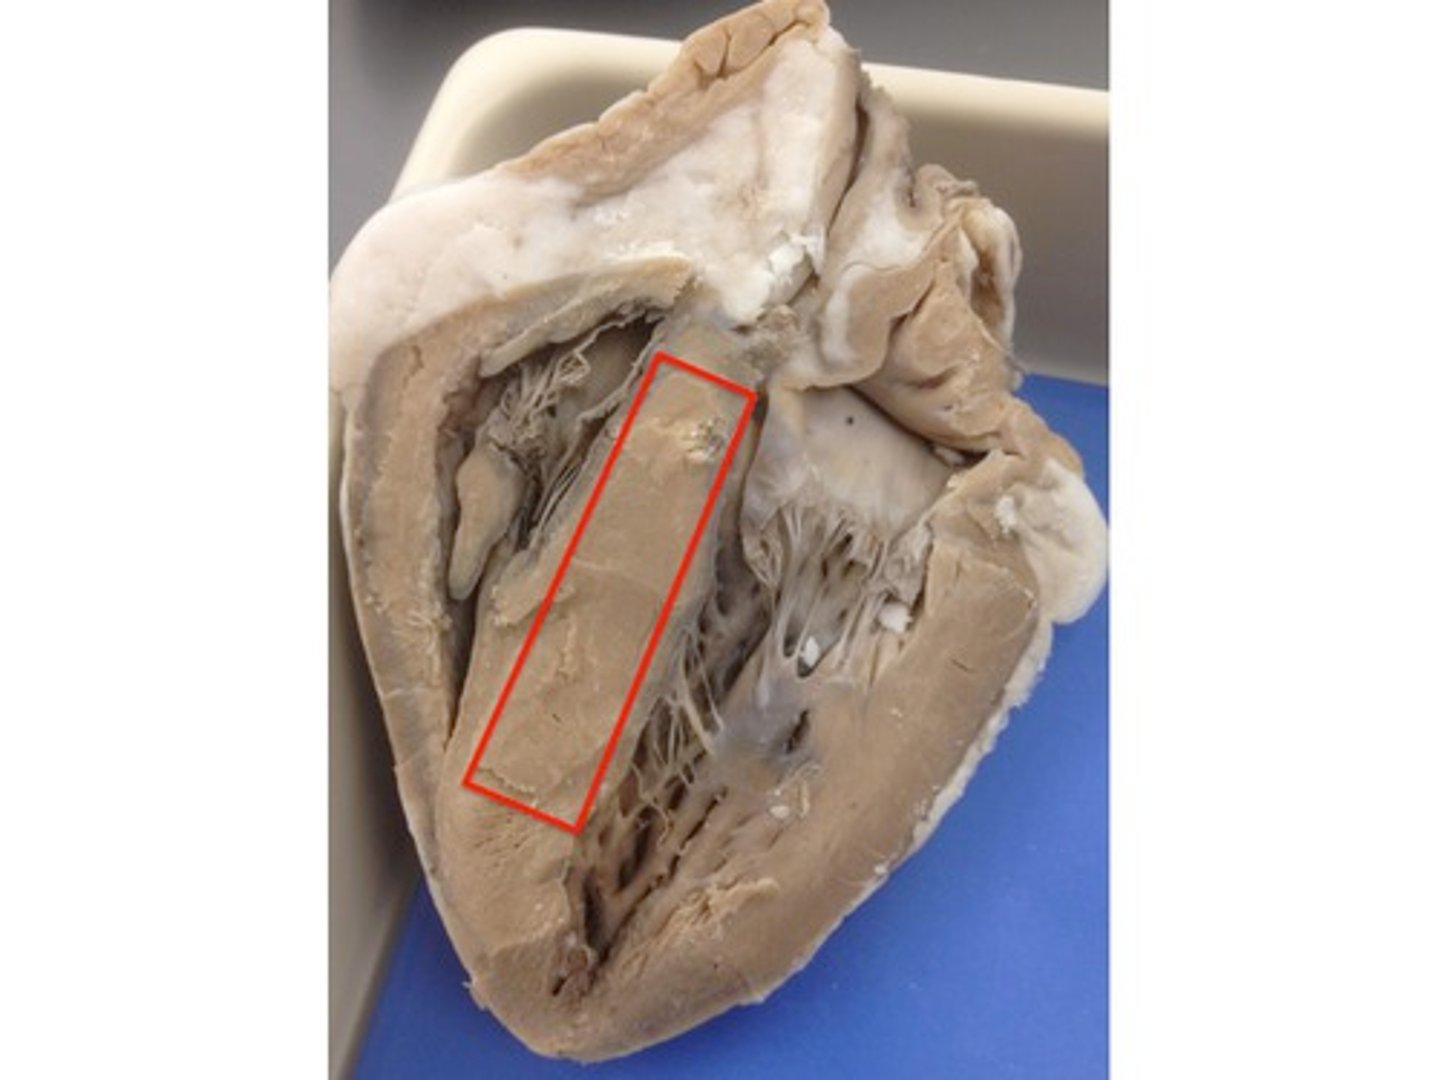

interventricular septum

Structure; separates the ventricles, pinch

H7

muscular part of the inter ventricular septum

THICK part of the septum

upper portion

membranous part of the inter ventricular septum

THIN part of the septum

lower portion

BQ: thin-uppermost part the site of ventricular septal defects (common birth defects)

Right atrioventricular orifice

Space, stick probe from atrium to ventricle to open doorway

H5

tricuspid valve

Structure; closed door, three flaps

26

R papillary muscles

Structure; right ventricle,

orange part of the carrot

tendinous cords

Feature; right ventricle

leaves of carrot

trabeculae carneae

Structure; in right ventricle

dirt of carrot

R/L